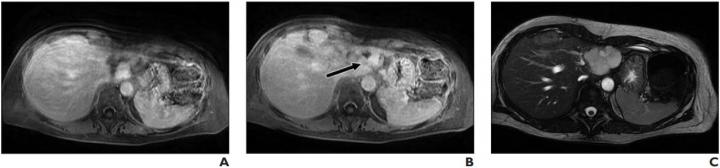

Lesion was originally reported as indeterminate enhancing mass, and outside report recommended biopsy. Classic features of benign hemangioma are shown. Error was attributed to faulty reasoning. A, Axial MR image obtained 5 minutes after contrast agent administration shows peripheral nodular discontinuous enhancement. B, Axial MR image obtained 10 minutes after contrast agent administration shows centripetal progression of enhancement (arrow). C, Axial fast imaging employing steady-state acquisition (FIESTA) MR image shows lesion is homogeneously hyperintense compared with liver parenchyma. Image courtesy of American Roentgen Ray Society (ARRS), American Journal of Roentgenology (AJR)